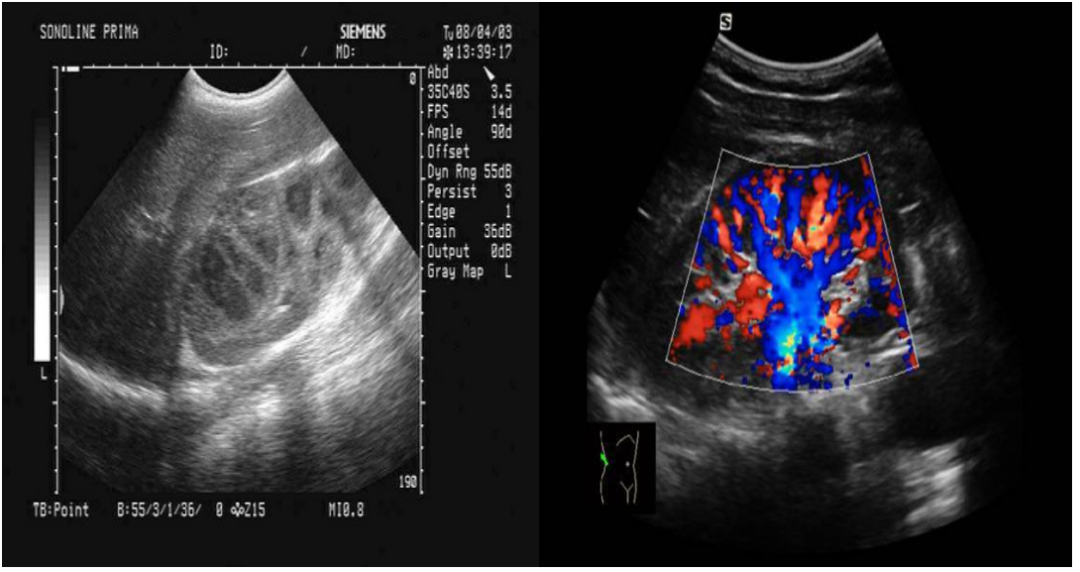

△左图为“黑白超声”,右图为“彩色超声”

彩超即彩色多普勒血流显像,英文缩写是CDFI,简单来说,彩超是高清晰的黑白B超再加上彩色多普勒,是一种复合图像,就是将所获得的多普勒信息进行处理,通过彩色灰阶编码,以不同的颜色和亮度分别标识血流的方向和速度以及性质,并叠加于B型超声声像图上。

彩超血流的特点是颜色代表血流的方向,即红色代表血流方向朝向探头,蓝色代表血流方向背离探头;色调的亮度表示速度,即色调的亮度越亮表示速度越高,色调的亮度越暗表示速度越低;血流颜色的单纯代表是层流,是正常的血流。五彩镶嵌的花色血流信号代表是湍流或涡流,说明血流性质有改变,多见于狭窄处的血流以及返流。

由此可见,彩超既具有二维超声结构图像的优点,又同时提供了血流动力学的丰富信息,实际应用受到了广泛的重视和欢迎,在临床上被誉为"非创伤性血管造影”。